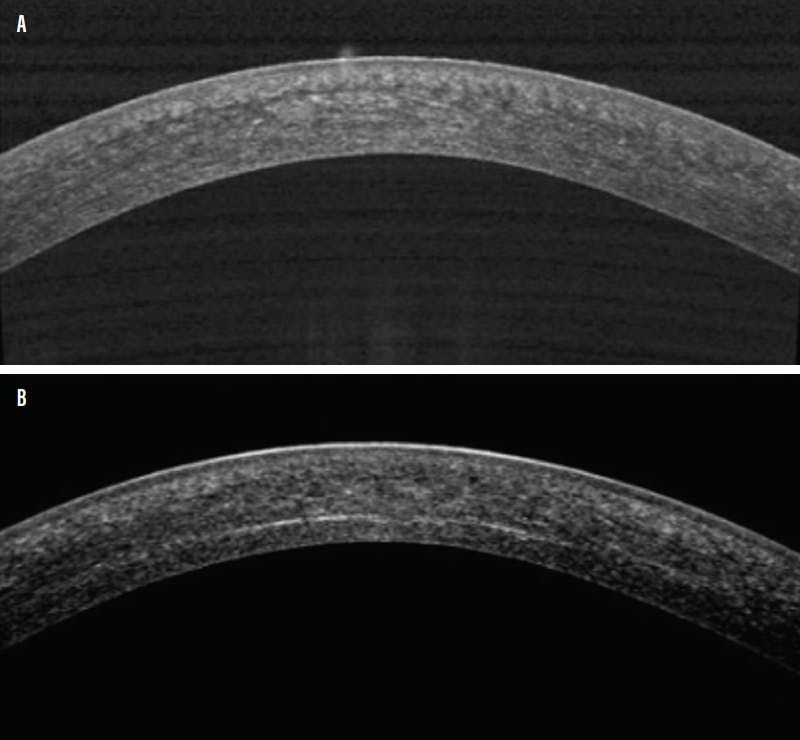

Because this procedure aims to strengthen the corneal tissue and slow ectasia, it is reasonable to expect that it produces anatomic changes in the cornea. Typically, there are increased bonding connections within the corneal stroma and a flattening effect on the cornea as keratometry values decrease.3 In addition to these beneficial outcomes, there are also potential adverse side effects, including corneal haze and scarring. Corneal haze typically fades over time, sometimes still changing through 1 year after CXL, but there are rare instances in which the haze may persist and lead to compromised vision,4 which may not be correctable even with specialty contact lenses.

Immediately after CXL, a soft bandage contact lens is placed on the cornea, and the patient is instructed to use topical medications to expedite healing of the eye and prevent infection. The bandage lens is typically removed after 1 week, when the epithelium has regenerated and healed. Studies show that corneal remodeling occurs during the first few months (Figure 2).2 During this time of remodeling, it is most practical to have patients wear the glasses prescribed to them before CXL.